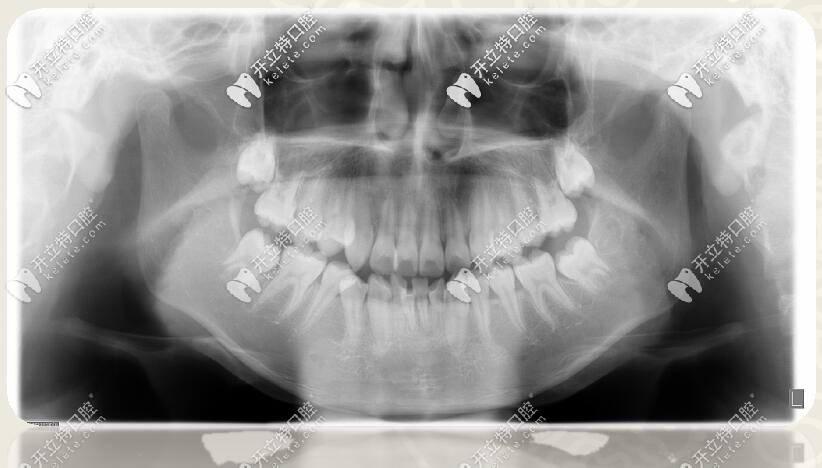

口腔全景片

1、安氏Ⅱ類(lèi)錯(cuò)合

2、骨性二類(lèi)錯(cuò)合

3、前牙區(qū)深覆蓋、深復(fù)合

4、跨牙合

5、牙列擁擠不齊